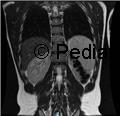

A 6-week-old male infant was brought to the emergency department with a three-day history of irritability, decreased food intake and a polymorphic skin eruption. He had no significant medical history, was exclusively breastfed with good weight gain. None of his family members had similar symptoms or lesions. The infant was in good general condition. Skin examination revealed an erythematous base with scattered vesicles, pustules and papules. The lesions were more prominent on the scalp, back and abdomen, including the neck, inguinal and axillary regions (Figure 1). Blood parameters were within reference ranges for age, with no increased inflammatory markers. Nevertheless, due to the exuberance of the lesions, a bacterial infection was suspected and intravenous flucloxacillin was initiated.

Figure 1A and 1B. Lesions in the torso: scattered vesicles, pustules, papules and nodules in an erythematous base.